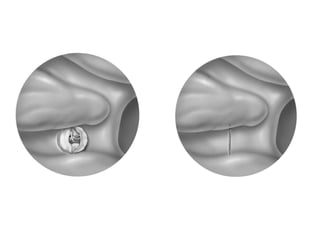

Schémas d’une embolisation d’anévrysme à l’aide de coils.

A. Cathétérisme du sac.

B. Vue finale après détachement du coil et retrait du microcathéter.

A B